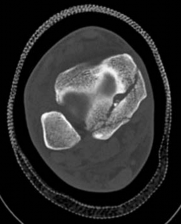

Standard orthogonal radiographs (anteroposterior and lateral) are sufficient for initial diagnosis, but they routinely underestimate the complexity of partial articular fractures. A high-resolution computed tomography (CT) scan with two-dimensional multiplanar reformats (coronal and sagittal) and three-dimensional surface rendering is considered the standard of care.

CT imaging is critical for:

1. Identifying the exact location and size of the articular fragments.

2. Detecting central articular depression that is obscured by the cortical rim on plain films.

3. Mapping fracture lines extending into the diaphysis.

4. Planning the surgical approach to ensure direct access to the primary fracture line.

Image